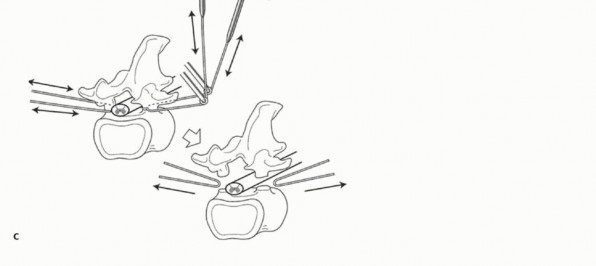

The following tissues serve as barriers to spinal tumor progression: the anterior longitudinal ligament (ALL), the posterior longitudinal ligament (PLL), the periosteum abutting the spinal canal, the ligamentum flavum (LF), the periosteum of the lamina and spinous process, the interspinous ligament (ISL), the supraspinous ligament (SSL), the cartilaginous endplate, and the cartilaginous annulus fibrosus. However, both the PLL and the periosteum on the lateral side of the vertebral body are “weak” anatomic barriers. In contrast, the ALL, cartilaginous endplate, and annulus fibrosus are “strong” barriers. In the spine, one vertebra could be regarded as a single oncologic compartment and the surrounding tissues as barriers to tumor spread (FIG 1).5

FIG 1. Compartment and barrier. SSL, supraspinous ligament; LF, ligamentum flavum; PLL, posterior longitudinal ligament; ALL, anterior longitudinal ligament; CL, capsular ligament; ISL, interspinous ligament.